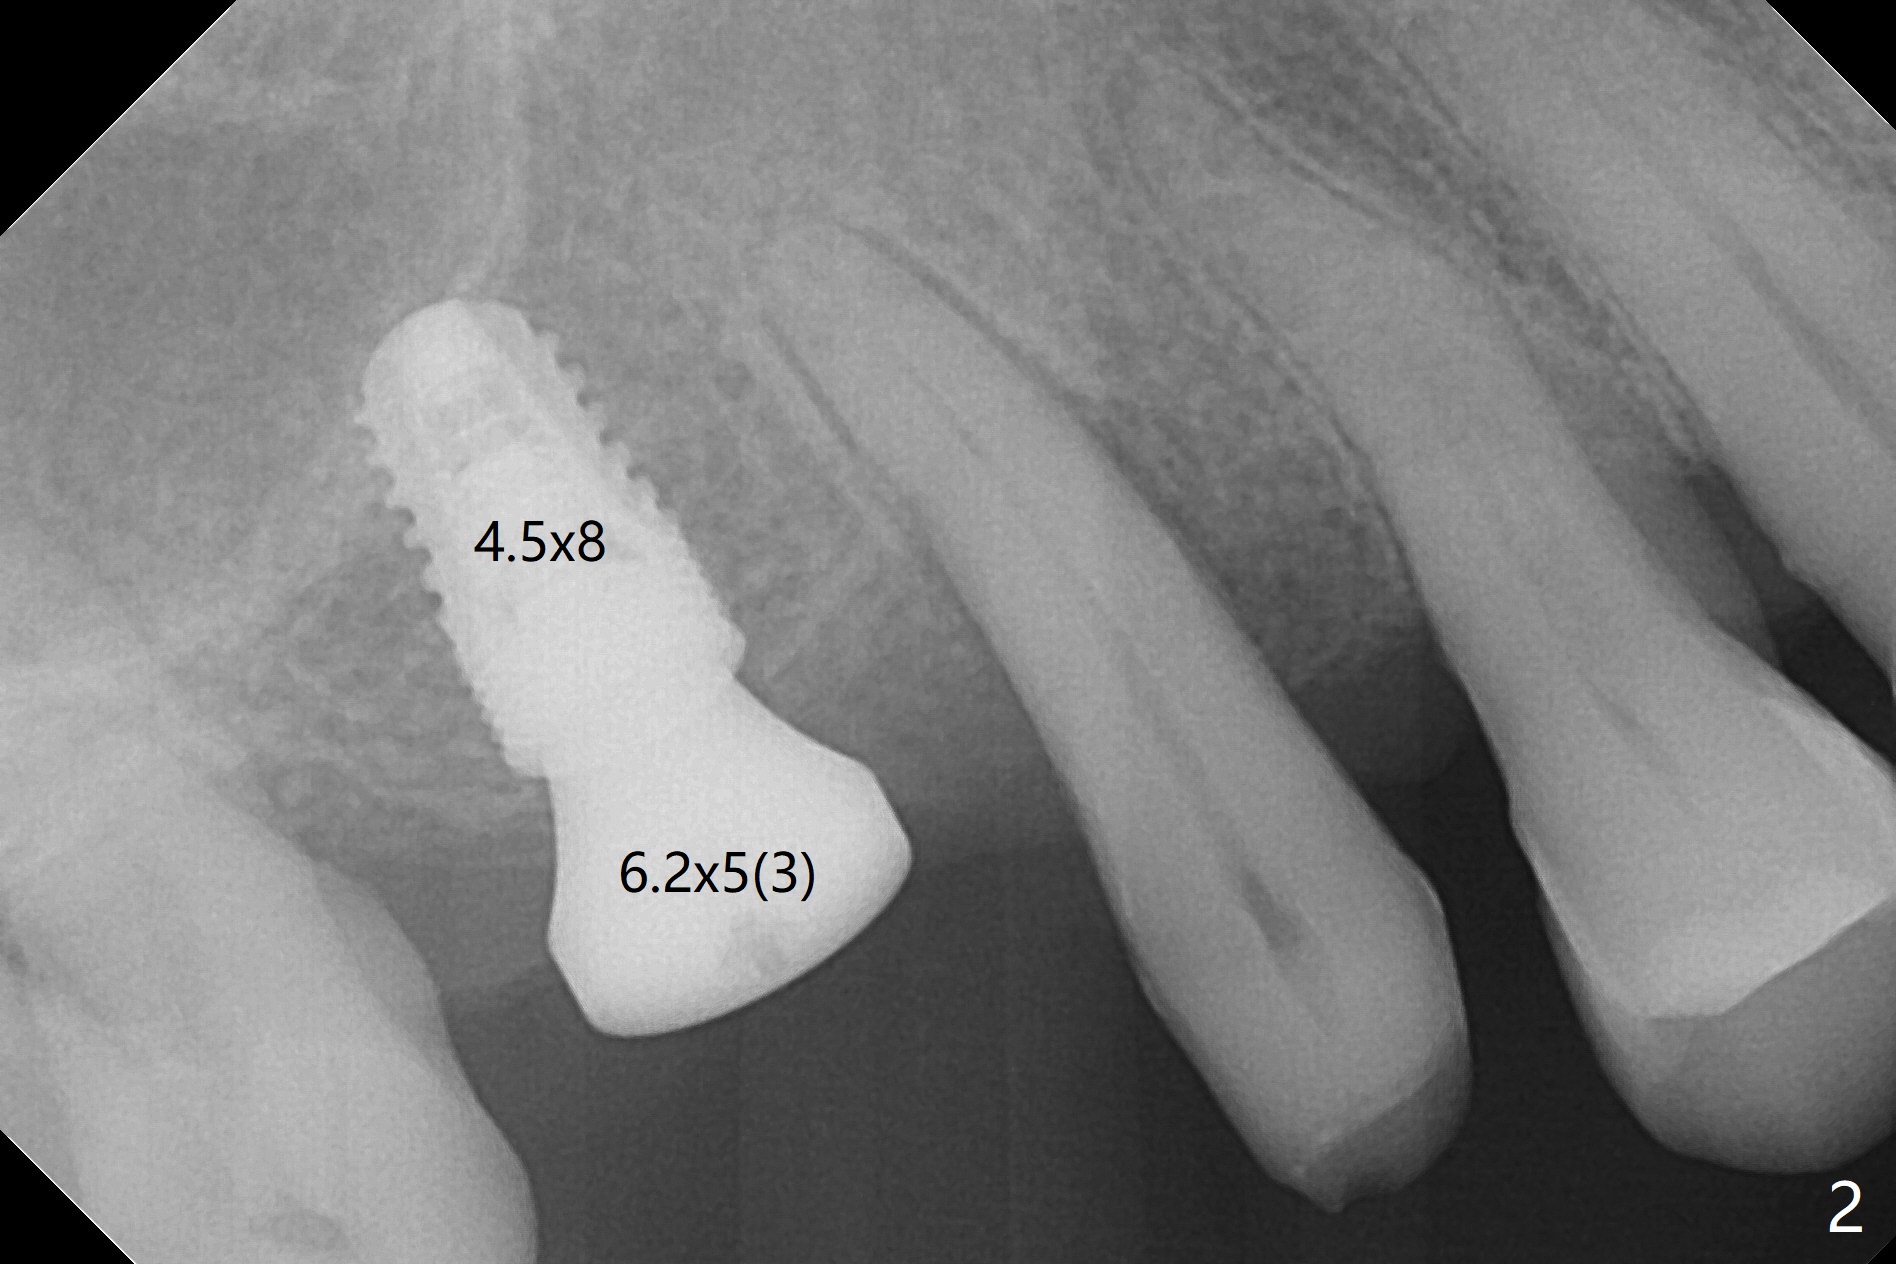

After osteotomy at #3 with IS guide, a 4.5x8 mm SM implant has to be placed free hand because of mismatch of the SM implant and IS guided fixture driver. With minor adjustment, the implant is placed subcrestal to reduce chance of future periimplantitis (Fig.1,2). There is oozing in the osteotomy, which seems to stop when the implant and healing abutment are placed. The patient returns with oozing next day. The temporary FPD is removed. The oozing is coming from the area around the healing abutment. Gauze pressure appears to be effective. After application of periodontal dressing (Fig.3 D) around the healing abutment, the temporary FPD is inserted (T). Hemostasis occurs. Fig.3 is taken 7 days postop. The implant remains subcrestal 3 month postop (Fig.4). A 5.8x7(3) mm cemented abutment is placed for a separate provisional.